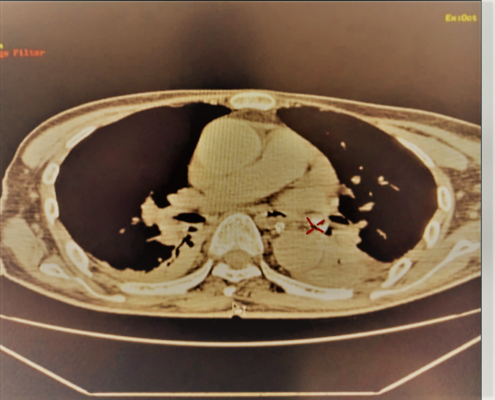

BSCKI Nguyễn Hữu Hạnh cùng ekip nội soi đã tiến hành nội soi phế quản ống mềm có gây mê để khảo sát toàn bộ đường thở của bệnh nhân. Khi đưa ống nội soi đến phế quản thuỳ dưới phổi trái, phát hiện một dị vật to bằng đầu ngón tay út, có nhiều góc cạnh, đờm và mủ bao phủ bên ngoài, dị vật che lấp gây tắc hoàn toàn phế quản S8, S9, S10 trái. Ngoài ra, dị vật di động theo nhịp thở, cọ vào thành phế quản gây chảy máu trong lòng phế quản. Ekip nội soi đã tiến hành các kỹ thuật lấy dị vật thông qua nội soi khí phế quản bằng ống mềm, dị vật là một răng rụng.

Dị vật phế quản thùy dưới trái Hình ảnh dị vật sau khi được lấy ra

Sau khi được lấy dị vật ra khỏi đường thở, bệnh nhân được tiếp tục theo dõi và điều trị, tình trạng khó thở cải thiện. Đây là trường hợp khá hy hữu, dị vật rơi vào phế quản nếu không phát hiện và lấy dị vật thì sẽ tiến triển nguy hiểm hơn: có thể bị xẹp phổi, mất chức năng, hoặc hoại tử, gây nguy hiểm tới tính mạng người bệnh.